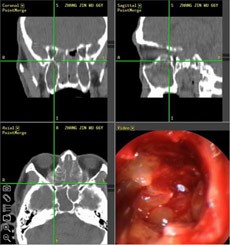

【典型案例】反复手术切息肉 复发导致嗅觉减退5年之久

张先生家住兰州,是典型的鼻窦炎患者,经常会出现鼻塞、流脓涕、头痛、等症状,去过多家医院,治疗结果并不理想,复发不说,到现在张先生的嗅觉已经严重减退,味道都快闻不出来了。

经推荐,跨省来到西安新城中大耳鼻喉医院耳鼻喉科治疗,入院后,经医生诊断并推荐使用“”,在鼻内窥镜的帮助下切除鼻息肉,术后经过10天后复诊并无复发现象。

(图为:鼻窦炎患者治疗现场) (图为:鼻窦炎治疗图谱)